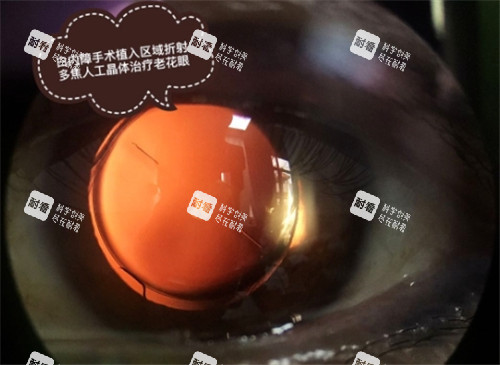

晶體選擇:免費≠“低質量”,國產晶體技術成熟

“免費手術用的晶體是不是質量差?”這是許多患者的顧慮。實際上,國產折疊晶體已通過各國藥監(jiān)局認證,技術成熟,術后結果與進口晶體差異不大。例如,某國產單焦點晶體市場價約2000元,已廣泛應用于免費手術,患者術后視力修養(yǎng)良好。若追求更高品質,可自費升級至多焦點晶體(市場價1.2萬-3萬元),但需評估自身經濟能力。